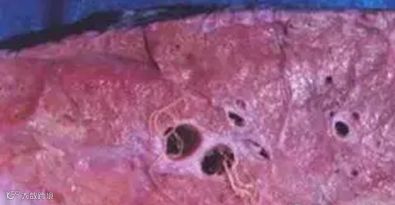

肺丝虫:

肺线虫,学名叫:后圆线虫病;是白色或乳白色的丝状,所以人们都叫肺丝虫;肺丝虫家族有三个品种,分别是:后圆线虫、长刺后圆线虫、复阴后圆线虫。都喜欢生活在动物的气管。身高大约都在11—25毫米,宽0.16—0.3毫米,挺瘦吧,要不怎么叫丝虫呢。都是卵生的,卵是椭圆形的。